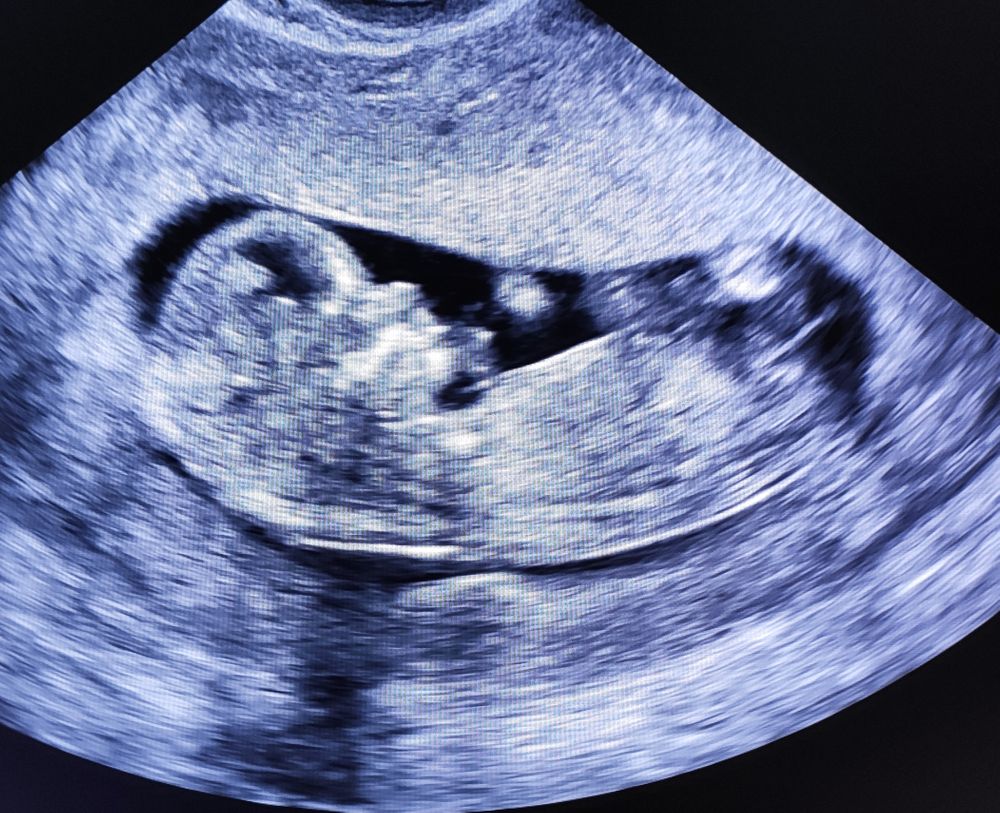

По УЗИ всë замечательно, там такой человек уже 😍 Идёт срок в срок.

Желающим погадать оставлю ниже единственный снимок, который у меня есть с этого УЗИ))) Даже интересно, кто и что увидит (Я ничего не вижу лично на этом снимке))

Ну и, собственно, фото пузожителя, любителям погадать: